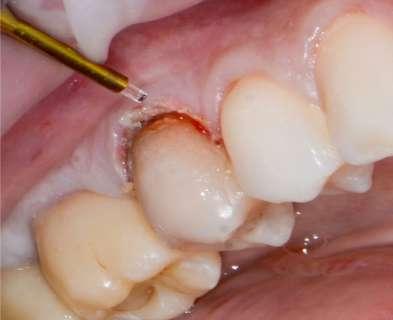

Trattamento di carie cervicale di elemento 1.5 con laser a Erbio

1 2

Paziente femmina, 38 anni che presenta carie cervicale dell’elemento 1.5. Gengivectomia con manipolo angolato, tip in zaffiro con diametro di 400 μm, lunghezza 12 mm, 2.4 W, 20 Hz, 120 mJ E per impulso, potenza di picco 750 W, densità di potenza media 659 W/cm2, densità di potenza di picco 205,860 W/cm2, energia totale 432 J, larghezza impulso 160 μs, distanza tip-tessuto 1 mm, 50% acqua, 50% aria, tempo totale di trafamento 180 sec. Impostazioni dello smalto: manipolo angolato, tip in zaffiro diametro 800 μm, lunghezza 12 mm, totale energia 810 J, ampiezza dell’impulso 160 μs, distanza tip-tessuto 1 mm, 100% acqua, 70% aria, tempo di trafamento totale 180 sec.

Fig. 1 – Cavità su 1.5 Fig. 2 – Particolare della cavità del dente 1.5 Fig. 3 – Preparazione Laser Er:YAG Pluser con lunghezza d’onda di 2940 nm di LAMBDA DoctorSmile, Italia. Fig. 4 – Particolare della cavità dopo gengivectomia Fig. 5 – Particolare della cavità completata dopo la preparazione della dentina Fig. 6 – Restauro finale in composito (Asteria Tokuyama, Japan)